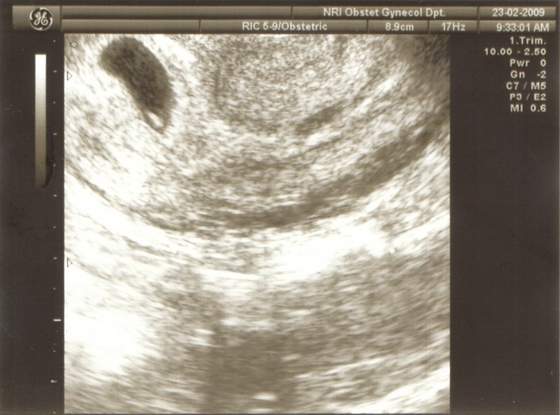

dziękuję shingle..na pewno jestem uspokojona tym bardziej, że wczoraj upadłam pod domem na oblodoznym chodniku i to na brzuch..wystraszylam się bardzo..zatem dzis szlam z dusza na ramieniu...i jak zobaczyłam bijace serduszko to od razu poczulam się lepiej..teraz bedę bardziej na siebie uważać